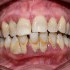

Paziente affetto da parodontite (piorrea) per scarsa igiene orale curato con le moderne tecniche di igiene, strumentazione ultrasuoni e manuale e con airflow Prophylaxis master. Con questo tipo di trattamento e con la costanza e la regolarità nelle sedute di igiene orale professionale periodica è possibile mantenere e salvare i propri denti senza dover ricorrere ad interventi di implantologia e protesi (dipende dalla gravità della situazione iniziale).

Da notare il miglioramento clinico della salute gengivale, la riduzione delle tasche parodontali e della presenza di placca e tartaro.